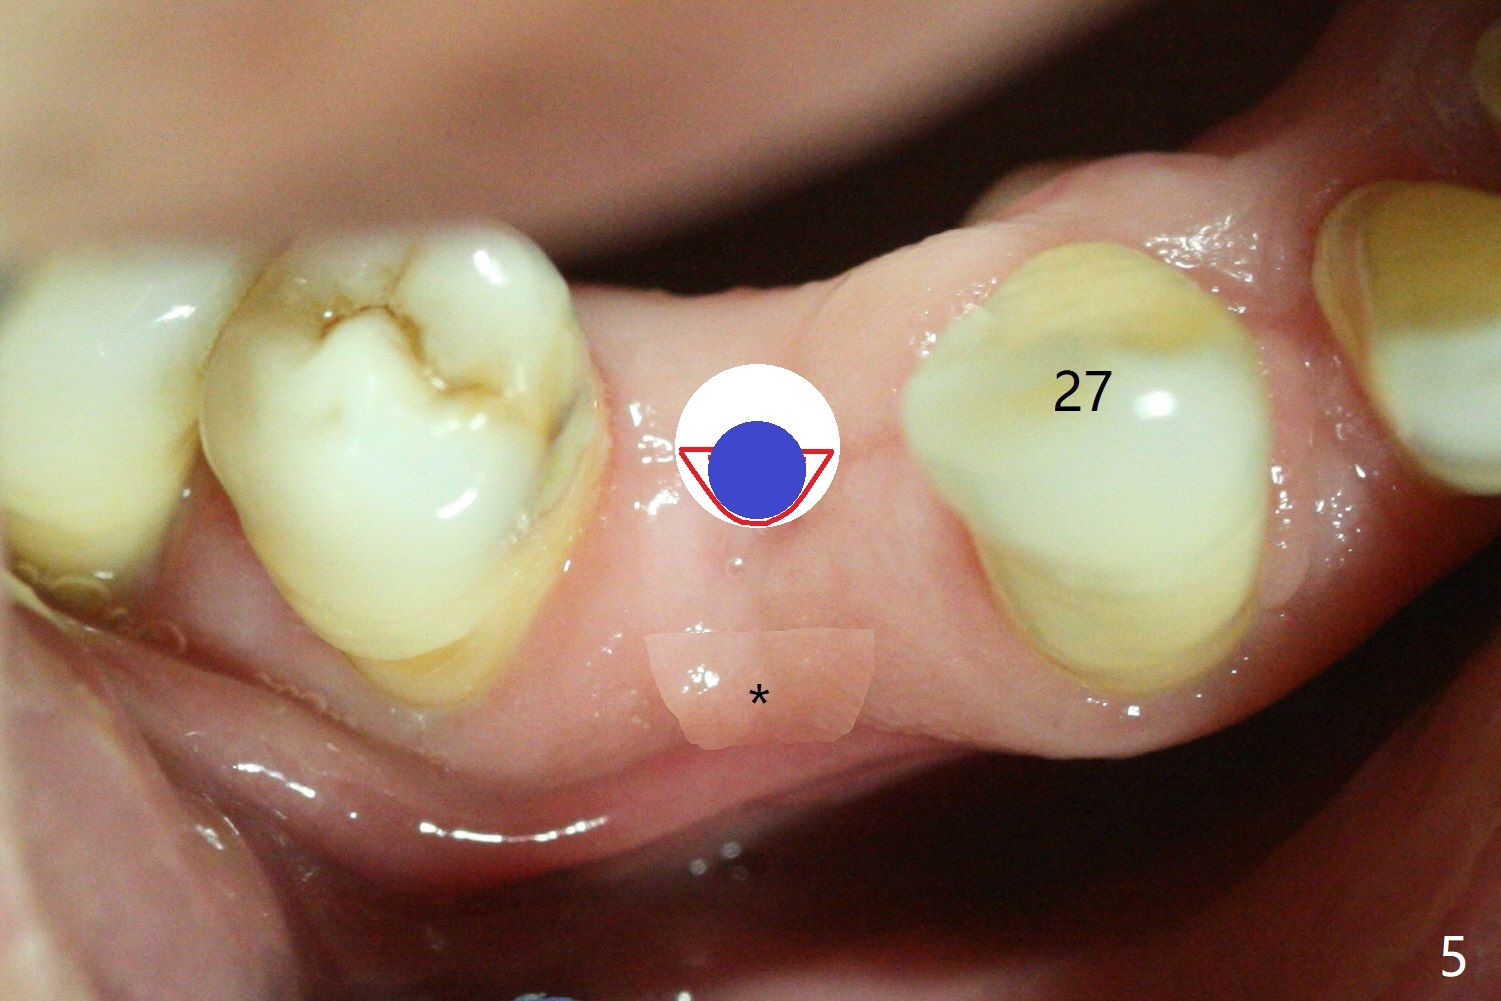

(Fig.3 red line). The buccal bone (Fig.4 red curved line) is

being expanded using a small DIO bone expander (blue circle). The buccal

plate is further expanded buccally with a large expander (Fig.5). Bone graft